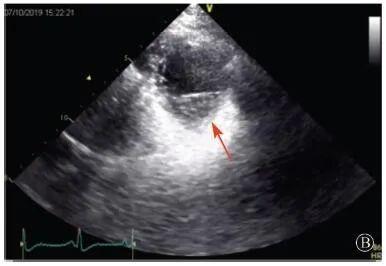

患者入院后無(wú)特殊不適,心率70次/min,血壓110/60 mmHg,心功能Ⅱ級(jí)。查血常規(guī):血紅蛋白139 g/L,白細(xì)胞7.39×109/L,血小板221×109/L。尿常規(guī)、便常規(guī)+潛血均正常。生化:丙氨酸氨基轉(zhuǎn)移酶38 U/L,白蛋白47 g/L,鉀3.9 mmol/L,肌酐(酶法)65 μmol/L,總膽固醇3.52 mmol/L,低密度脂蛋白膽固醇2.08 mmol/L。CK:1256→487 U/L,CK-MB 9.7→3.8 μg/L,cTnI 85.90→68.50 pg/ml。N末端B型利鈉肽原70 pg/ml。CK同工酶電泳:肌酸激酶MM質(zhì)量100.0%(此時(shí)CK-MB已正常)。血沉1 mm/第1小時(shí),高敏C反應(yīng)蛋白1.61 mg/L;補(bǔ)體:C3 0.876 g/L,C4 0.174 g/L。免疫球蛋白:IgG 9.52 g/L,IgA 1.73 g/L,IgM 0.62 g/L。血清蛋白電泳未見(jiàn)M蛋白。糖化血紅蛋白5.1%。乳酸(運(yùn)動(dòng)前)1.1 mmol/L,乳酸(運(yùn)動(dòng)中)6.6 mmol/L,乳酸(運(yùn)動(dòng)后)7.8 mmol/L。肌炎抗體譜:抗PM-SCL75(+),余均(-)。心電圖:aVL、V5、V6導(dǎo)聯(lián)T波倒置(圖2)。冠狀動(dòng)脈CT未見(jiàn)明顯異常。超聲心動(dòng)圖:左室舒張末內(nèi)徑55 mm,左室收縮功能減低,心尖部、左室壁普遍運(yùn)動(dòng)減低,以左室下后壁為著,左室下后壁肌小梁明顯增多可見(jiàn)隱窩,疏松層與致密層之比為1.7;左室射血分?jǐn)?shù)(雙平面)45%;右冠狀動(dòng)脈開(kāi)口6.5 mm,開(kāi)口處未見(jiàn)明確瘤樣擴(kuò)張(圖3)。

A:胸骨旁長(zhǎng)軸平面,左室舒張末內(nèi)徑略增大,室壁無(wú)明顯增厚;

協(xié)和疑難︱第67例:臨床表現(xiàn)胸痛伴肌酸激酶升高

B:胸骨旁左室短軸切面心尖水平,可見(jiàn)心肌肌小梁增多,其內(nèi)可見(jiàn)隱窩(箭頭所示)

圖3 患者入院后超聲心動(dòng)圖